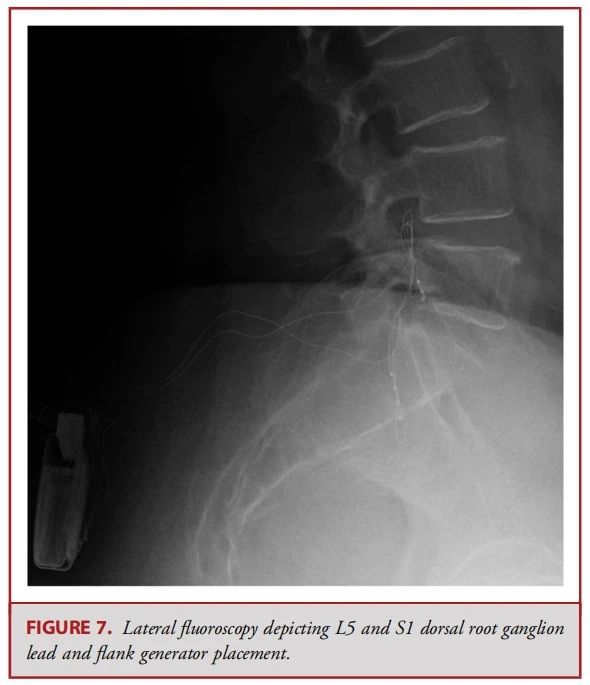

● 背根神经节(DRG)刺激器导线的置入传统上可通过对侧的旁中线途径。此时,Tuohy针穿刺点位于椎体旁,距离目标椎孔约2个椎体水平。使用失去阻力法将针头推进至接近中线的尾端椎板间隙。一旦进入硬膜外腔,导管鞘会被调整方向,使其指向目标椎孔,并缓慢推进。接着插入导丝,然后插入导线;使用透视法确认导线位置。最后,在硬膜外腔内形成一个应变缓解的“S”形环,并将导线固定在深筋膜上(见图 2、6 和 7)。